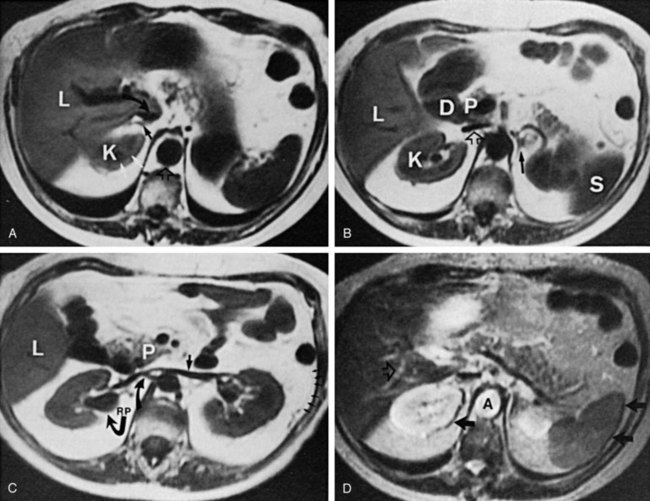

Because magnetic resonance imaging (MRI) offers previously unseen detailed soft tissue imaging compared with CT, it was initially believed that MRI would not require contrast enhancement. However, by 2005, almost 50% of MRI studies were being performed with contrast media. Extracellular MRI contrast agents contain paramagnetic metal ions. Copper, manganese, and gadolinium were the potential paramagnetic ions for use with MRI. Gadolinium, however, is the most powerful having seven unpaired electrons, but its toxicity required encapsulation by a chelate. Paramagnetic agents like gadolinium are positive enhancers reducing the T1 and T2 relaxation times and increasing tissue signal intensity on T1-weighted images, while having little effect on T2-weighted images.